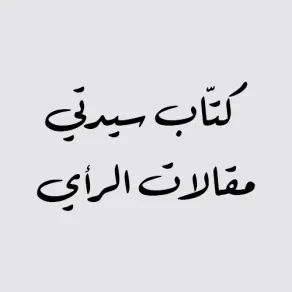

ويكشف عرضه التفاعلي أعضاء جسم الإنسان كافّة، بالصوت والصورة والمجسّمات.